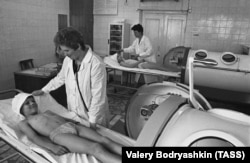

Существует в российской медицинской практике довольно сомнительное наследство, доставшееся от СССР, и имя ему – физиотерапия. Это целый букет полунаучных методов, использование которых, в отличие от "Кремлевской таблетки", в Советском Союзе было полностью узаконено и распространено. Всяческие "электрические" УВЧ-прогревания, электрофорез, магнитотерапия. Они расцвели пышным цветом в те же 80-е годы, когда надо было освоить полтора миллиарда рублей, выделенных на медицинский прогресс.

Поэтому в позднем СССР любой ушиб или боль в ухе лечили с помощью токов высокой частоты, а электрофорез использовали при приеме многих лекарств (он будто бы усиливал их действие). Плюс к этому больных обмазывали лечебными грязями или черным битумом (озокерит) и совершали над ними массу других скорее ритуальных, нежели медицинских действий… Впрочем, это происходит и сейчас, ведь кабинеты физиотерапии есть почти в каждой больнице.

В Европе и в США, где многое из этого тоже было когда-то популярно, от большинства подобных методов практически отказались. То есть они существуют – но не в рамках официальной медицины, а в частных клиниках, предлагающих нетрадиционные методы лечения. Все потому, что серьезные исследования, проведенные во второй половине XX века, не обнаружили никаких доказательств реальной действенности того, что в СССР назвали "физиотерапией". Да, особого вреда от нее нет, и психологически тоже помогает – но, согласно западным исследованиям, в большинстве случаев это не лекарство, а плацебо.

Конечно, найдутся тысячи людей, которые с этим поспорят. Им вот это все "реально помогло". И электрофорез, и УВЧ, и магнитики на руках. Врачи сошлются на свой многолетний опыт, доказывающий, что после физиотерапии люди выздоравливают. Возможно, так и есть. Однако "доказательная медицина" утверждает, что почти в ста процентах случаев больные точно так же выздоравливают и без нее.

Зато физиотерапия хороша тем, что с ней вроде как нельзя ошибиться! Считается, что даже если она не поможет, то уж точно не навредит. Поэтому кабинеты физиотерапии никогда из отечественных больниц не исчезнут. Тем более что с лекарствами и дорогим оборудованием начинаются проблемы – а незамысловатые приборчики для лечения электричеством и магнитными полями, выпущенные еще в прошлом столетии, не знают сноса и ремонтируются простым паяльником.

Есть такие приборы и в пенитенциарной системе России. И работают будь здоров. Например, футболисту Александру Кокорину, несколько лет назад попавшему в тюрьму за пьяную драку, пришло в голову пожаловаться тюремному доктору на ушиб лодыжки. Футболисту немедленно сделали электрофорез – и сожгли кожу и мышечную ткань на ноге, так что об ушибе он быстро забыл. Но, в конце концов, тюрьма не больница.